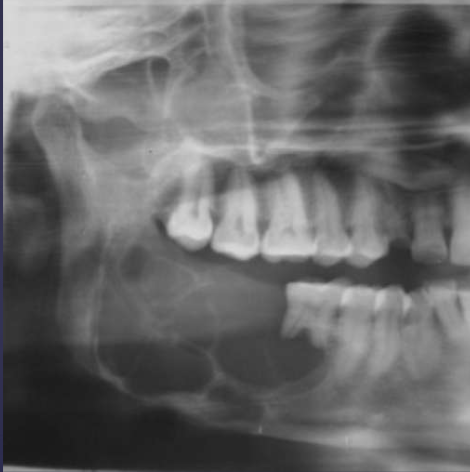

describe what’s occurring in this radiograph

pericoronal/mural; impacted tooth

displacement of #32 + IAN

osseous expansion

thinning of cortices